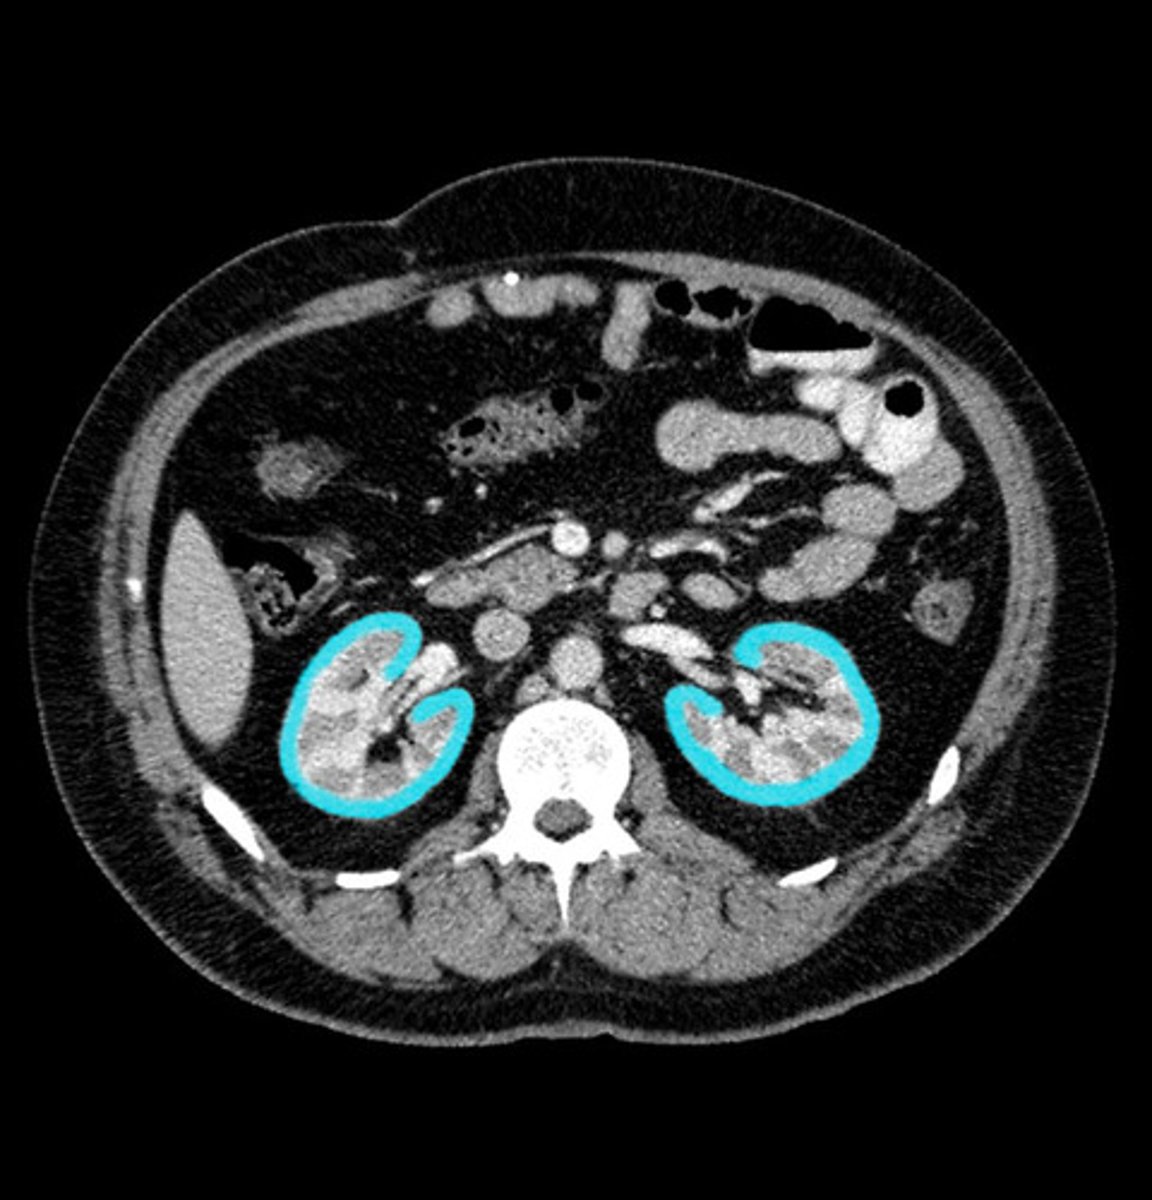

renal imaging

xray (IV pyelography)- mainly replaced by US and CT

US- size, symmetry, lesions, kidney stones, obstructions, hydronephrosis

CT- characterize US abnormalities, study of choice for nephrolithiasis, trauma

MRI- renal cell cancer, mass